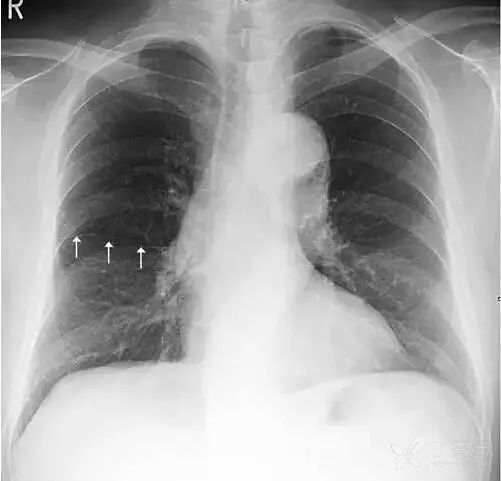

在解剖结构上,肺叶由叶间裂胸膜自然分隔而成,左肺由斜裂分为上、下2个叶,右肺由水平裂(横裂)和斜裂分上、中、下3个叶。胸部X线平片中,叶间裂胸膜和X线方向平行时可以显影,呈细线状。其中,正位胸片常可以看到右肺水平裂(图11)。

图11 右肺水平裂。正位胸片常可以看到细线状的右肺水平裂,位于右肺野中部,自肺野边缘向右肺门水平走行,水平裂以上为右肺上叶,以下为右肺中叶和下叶。